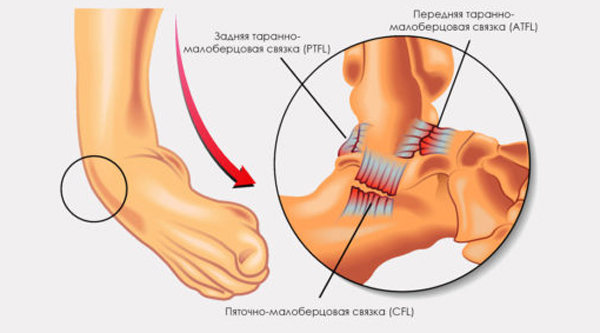

Движения ног обеспечиваются слаженной работой суставов, мышц, связок и сухожилий. Травмы голеностопного сустава чаще всего встречаются у молодежи. Разрывом называют частичное или полное повреждение связок, соединяющих кости голеностопного сустава, который формируется из таранной, большеберцовой и малоберцовой костей.

Различают полный разрыв, растяжение и надрыв связок. При полном разрыве концы связки могут расходиться, что приводит к нестабильности сустава. В таких случаях часто требуется хирургическое вмешательство, так как консервативные методы лечения не всегда эффективны. Повреждения голеностопных связок происходят реже, чем травмы коленных суставов. В некоторых случаях травма может быть комбинированной.

Разрыв связок голеностопного сустава может произойти в различных ситуациях. Часто такие травмы случаются дома из-за игнорирования правил безопасности. Основные факторы, способствующие травме, включают резкую инверсию (заворот наружной стороны стопы), эверсию (вращение наружу) и неосторожный поворот ноги. Связки голеностопа испытывают значительные нагрузки, и когда они превышают допустимые пределы, волокна связок могут рваться.